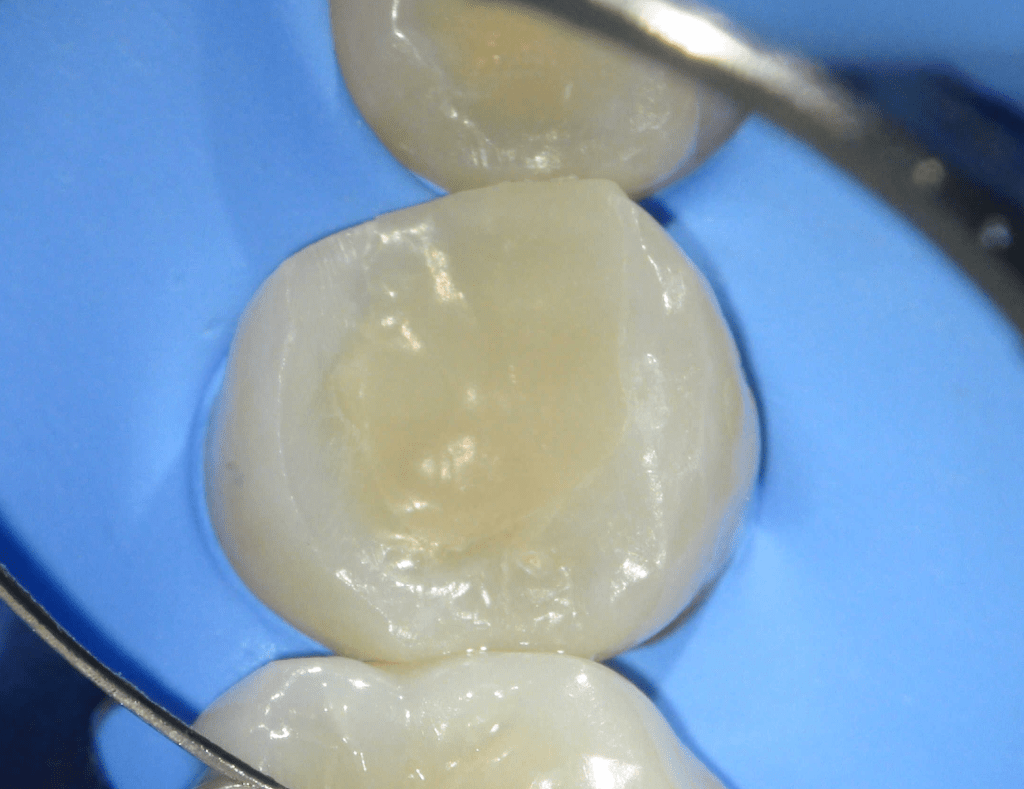

Pulpotomía biodentine + reco preendio